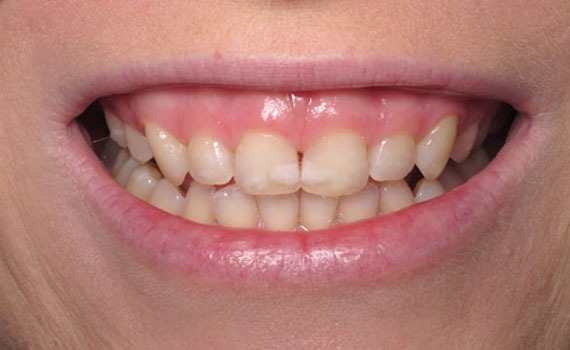

Ortodonti

Diş çapraşıklıkları çocukluk döneminde süt dişlerin yerini asıl dişlerin alması ile başlayan bir süreçtir.

Devamını Oku